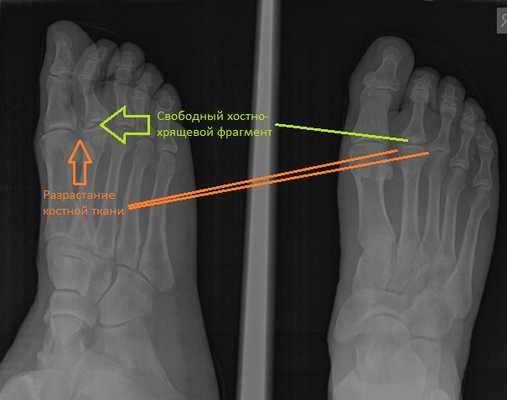

При клиническом осмотре определяется умеренный отёк в средней части переднего отдела стопы, при пальпации боль в проекции 2 плюсне-фалангового сустава. При оценке амплитуды движений во втором плюсне-фаланговом суставе провоцируется боль, движения качательные, амплитуда менее 5 градусов. На рентгенограммах отчётливо видны разрастания костной ткани в области головки 2 плюсневой кости и свободное внутрисуставное тело.